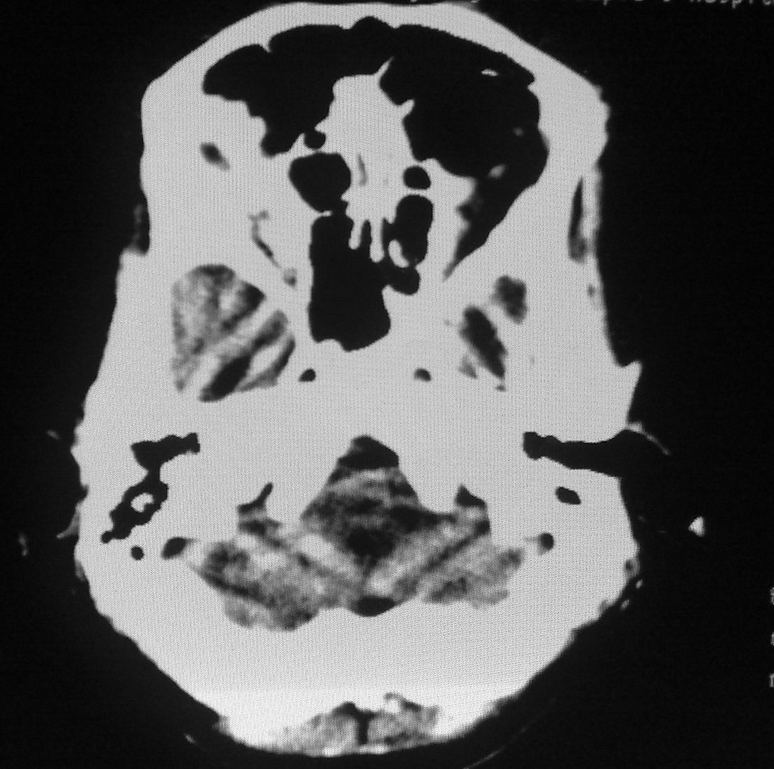

女,46岁,走路有时向一侧偏斜。是小脑萎缩吗?

小脑脑沟增多加深      为小脑萎缩引起的共济失调

小脑脑沟多于四条即为增多,又见加深,所以支持小脑萎缩。

从图像上看的确有轻度小脑萎缩征象,但患者才46岁,有外伤史吗?

小脑萎缩可能性大,建议mri检查。

小脑轻度萎缩